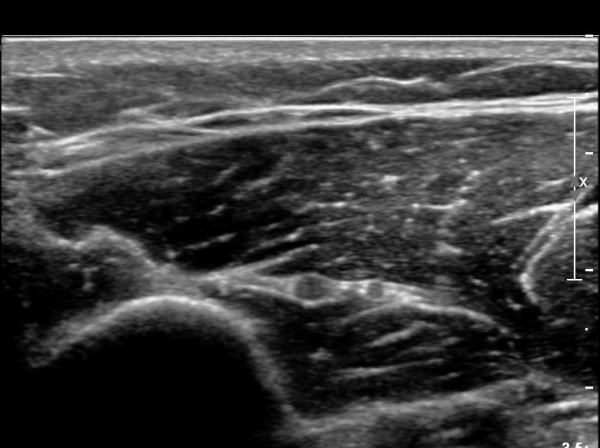

Á¶±Ý ´õ ¸»´ÜÀ¸·Î À̵¿ÇÏ´Ï ´Ù½Ã Àú¿¡ÄÚ ºÎÁ¾ »óÅ·Π°üÂûµÈ´Ù(»çÁø 4).

ÀÌ·± ÀÏ·ÃÀÇ °úÁ¤Àº ÷ºÎ µ¿¿µ»ó¿¡¼­ ¶Ñ·ÈÈ÷ °üÂûµÈ´Ù.